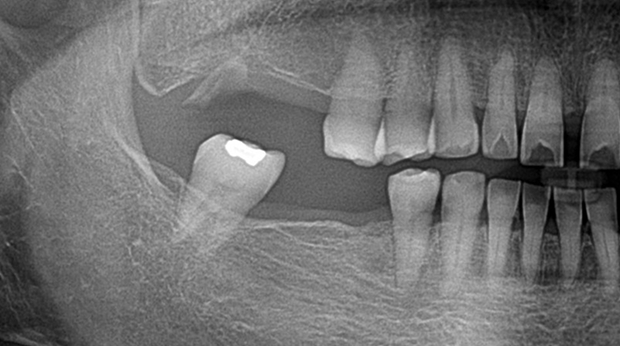

매복 사랑니 발치